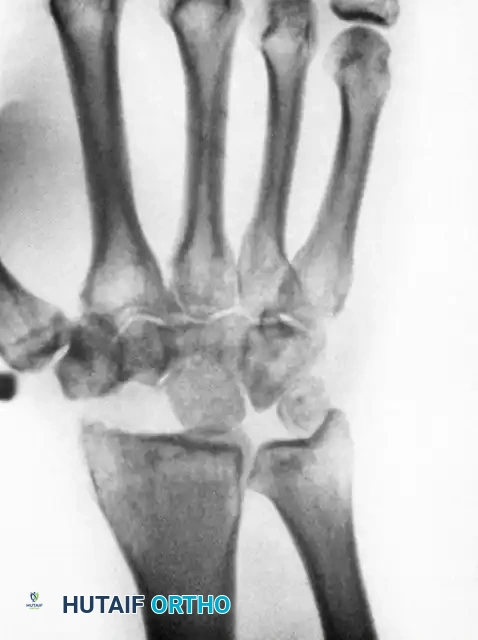

Image

Above: Postoperative radiographic appearance following a Proximal Row Carpectomy (PRC) combined with a radial styloidectomy. Note the smooth articulation of the capitate within the lunate fossa.